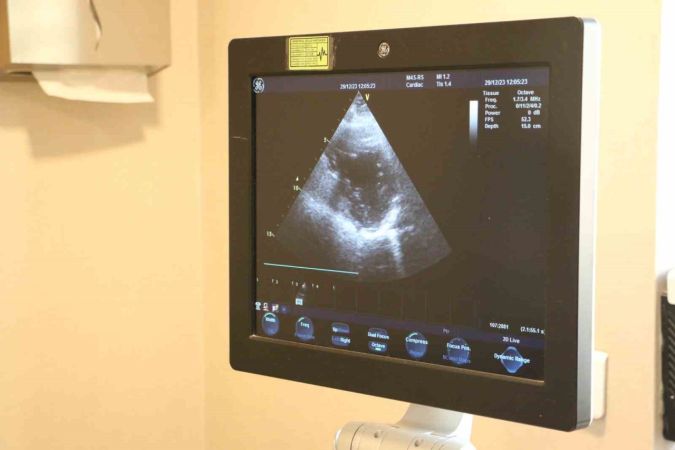

"Kalp kapak hastalıkları, kalp kapaklarının işlevini kaybetmesiyle ortaya çıkar. Zamanla yaşa bağlı olarak gelişebilir, enfeksiyon, travma ya da kalp krizi sonrasında da görülebilir. Kalp kapak hastalıklarının belirtileri, günlük yaşamı etkileyebilir ve ciddi sağlık sorunlarına yol açabilir."

Dr. Hüseyin Akçalı, kalp kapak hastalıklarının belirtilerini detaylıca açıklıyor. Bu belirtiler arasında en dikkat çekici olanı, ayaklarda görülen şişliktir. Erken tanı ve düzenli takibin bu hastalığın yönetiminde kritik bir öneme sahip olduğu vurgulanıyor.